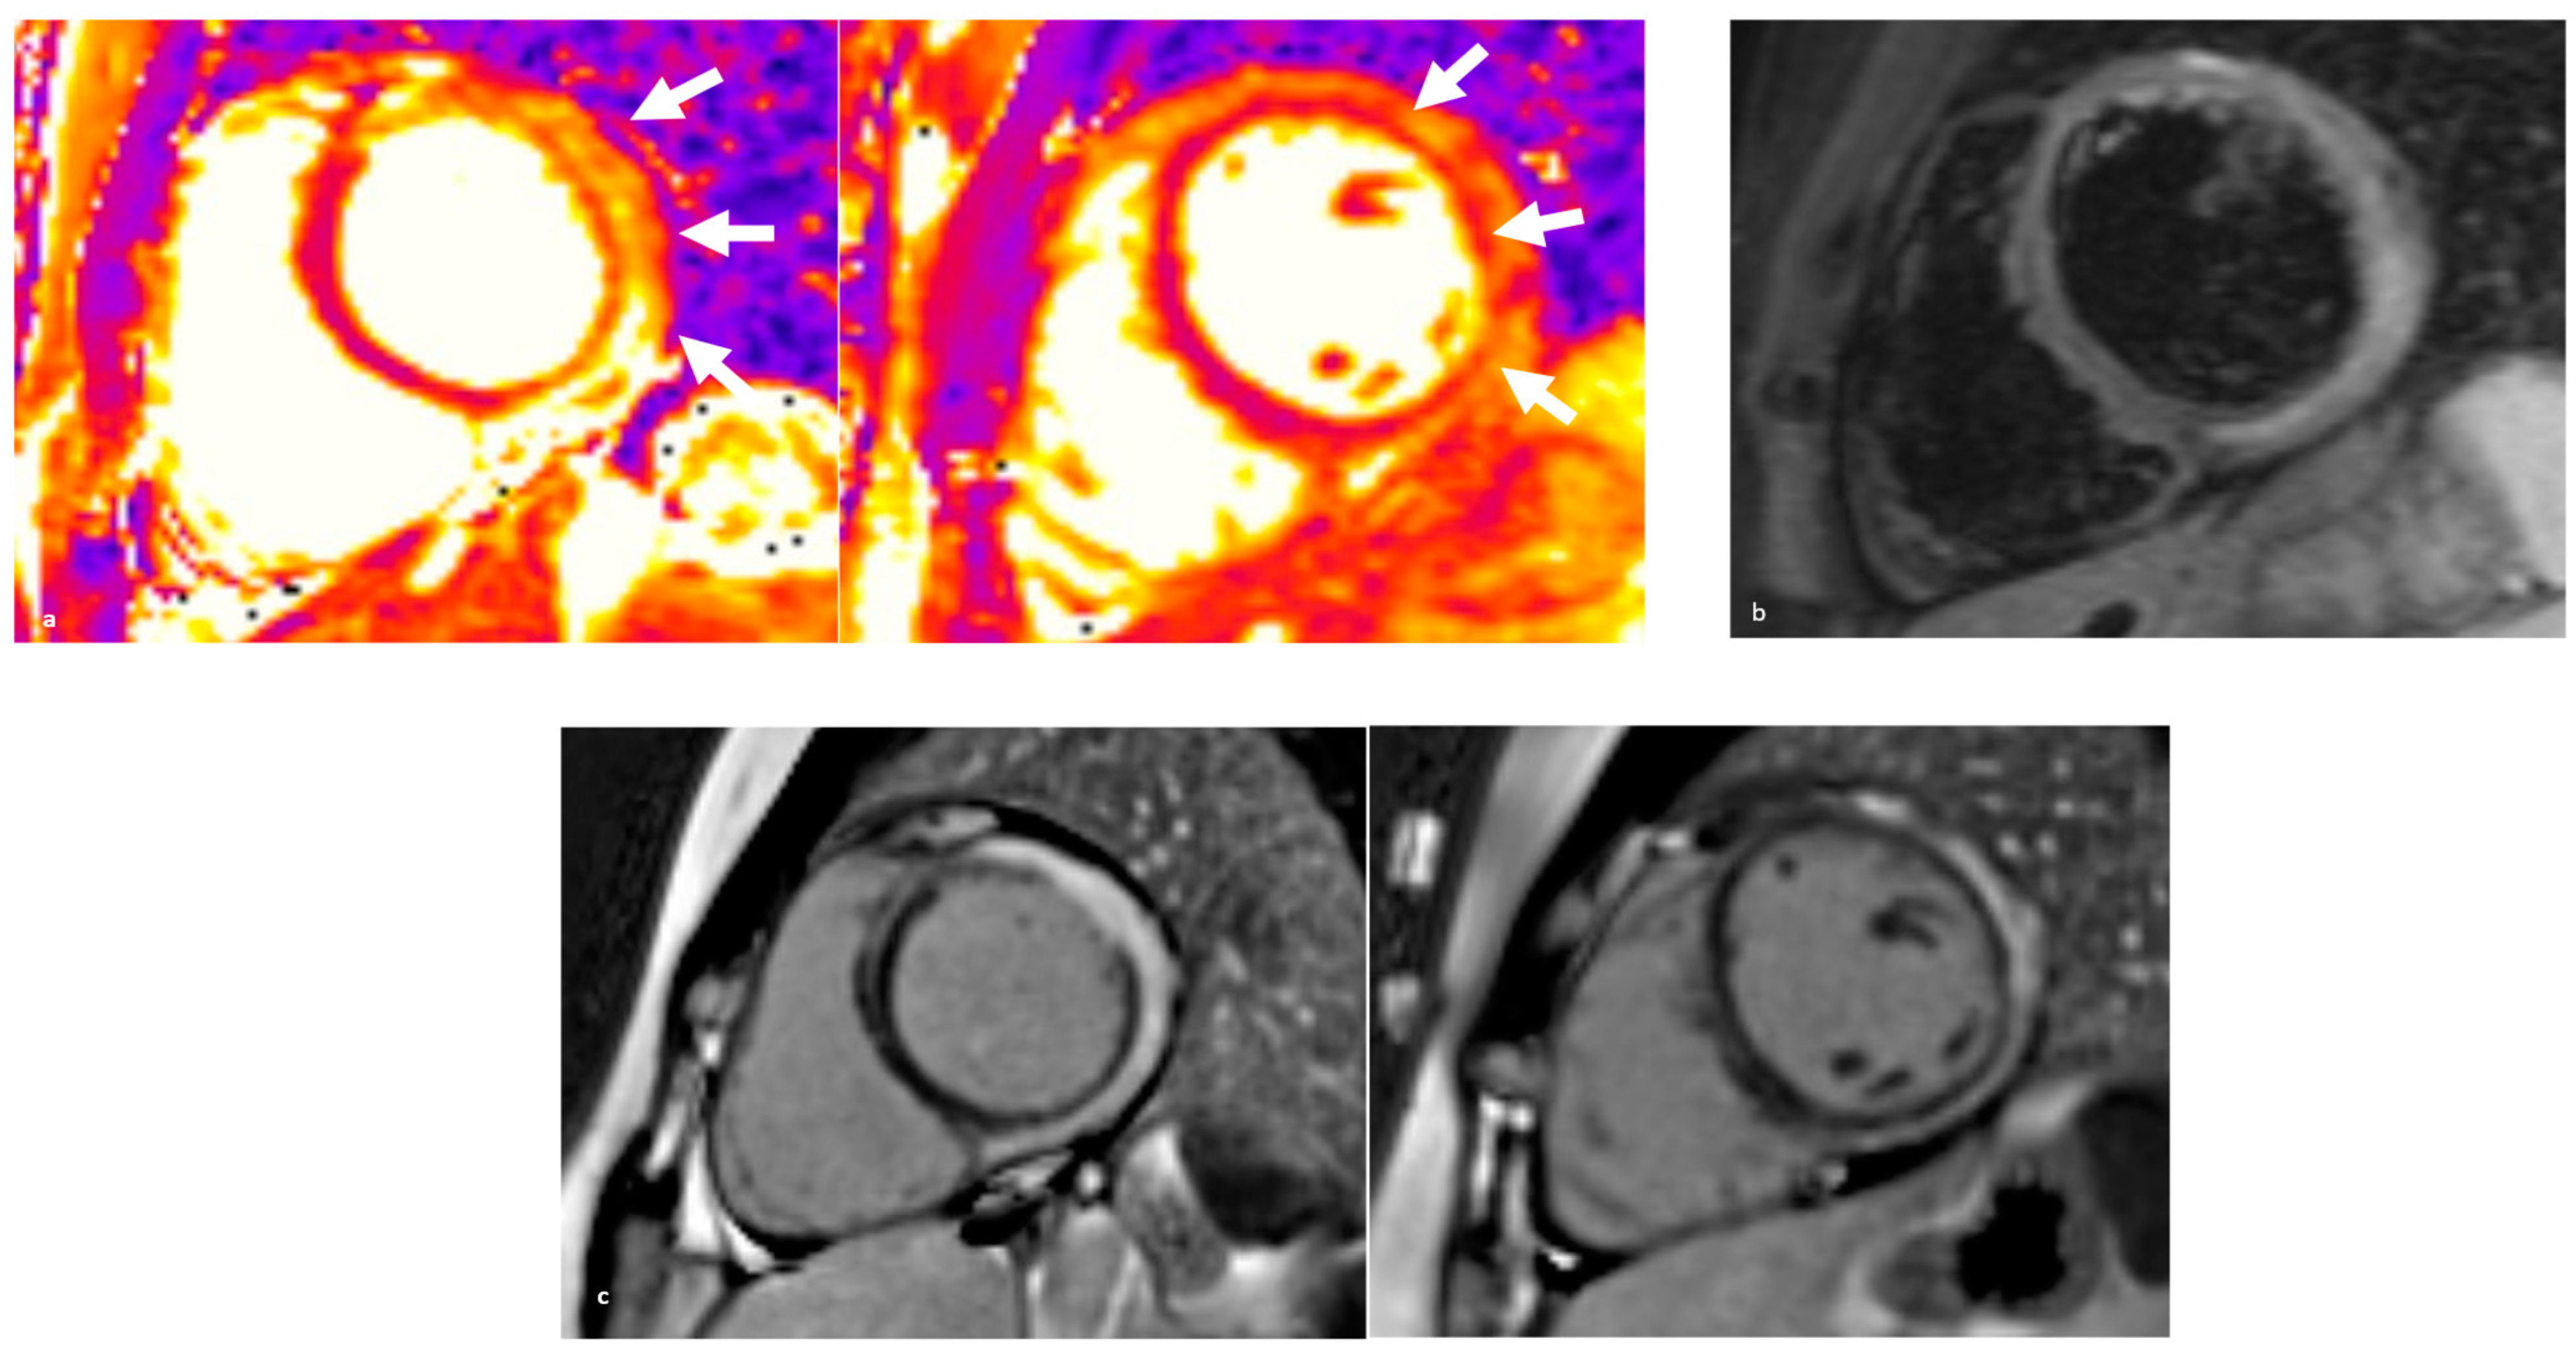

4.1.2. Diagnostics

4.2.2. Diagnostics

4.3.2. Diagnostics

4.4.2. Diagnostics

4.5.2. Diagnostics

5.3. Diagnostics